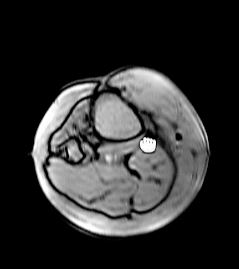

A kép nagyítható a bal és a jobb egérgomb együttes nyomva tartásával, és felfelé húzva nagyítható, lefelé húzva pedig kicsinyíthető. A kurzor nagyítóvá válik, míg el nem engedi az egér gombjait.

Egy kép mozgatásához azt először nagyítani vagy kicsinyíteni kell mindkét egérgombot lenyomva tartva, és felfelé vagy lefelé húzva

Ezután kattintson a bal egérgombbal, és húzza a képet. A kurzor zárt kézre változik, míg el nem engedi az egérgombot.

Nyomja meg és tartsa lenyomva a jobb egérgombot, miközben húzza az egeret. A jobbra és balra mozgatással növeli és csökkenti az ablak szélességét. A hátra és előre mozgatással növeli és csökkenti az ablak középpontját. Ha elengedi az egeret, az eRAD PACS frissíti a többi képet a sorozatban ugyanazt az eltolást használva.

Kattintson kétszer a bal egérgombbal bármelyik képkockára a teljes oldalas módba való belépéshez, majd kattintson kétszer a bal egérgombbal ismét a képkockához való visszatéréshez.